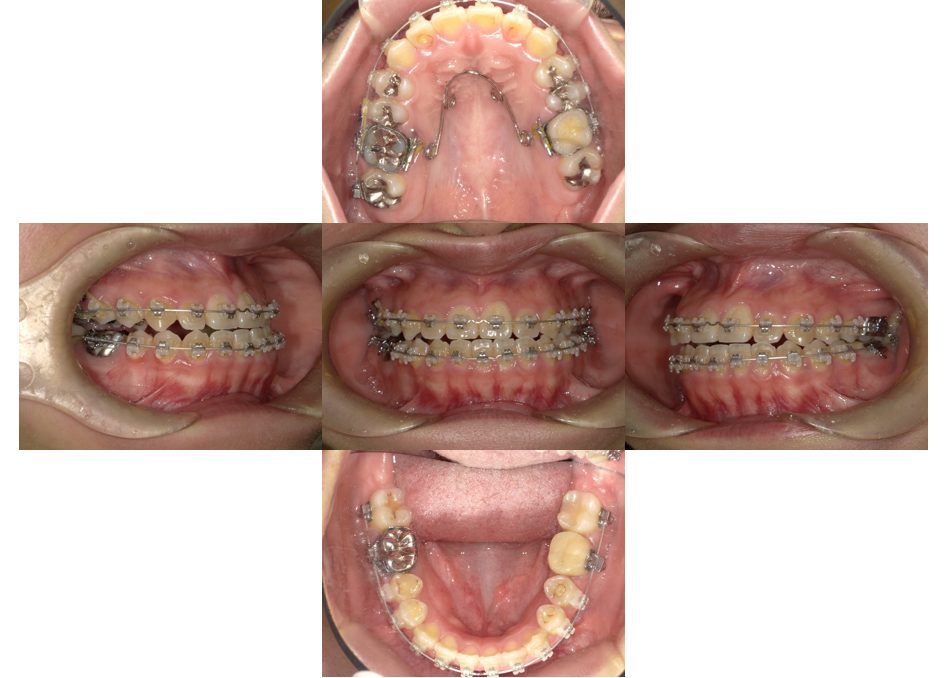

矯正治療・インプラント治療・セラミック治療の症例紹介(三隅歯科クリニック)

三隅 賢祐(三隅歯科クリニック)

症例詳細

| 主訴 | 30代女性 顎関節が痛い。見た目も気になる |

| 治療内容 | 矯正治療を行いました。 |

| 治療費 | 1,700,000円(税込み) |

| 治療期間 | 3年(矯正治療期間 2年半) |

| 治療回数 | 40回 |

| 想定されたリスク | 術前に精密な診査診断とシミュレーションを行い、インプラントを適正なポジションに埋入しておかないと、インプラント自体が矯正治療の邪魔になるリスクがあった。 |